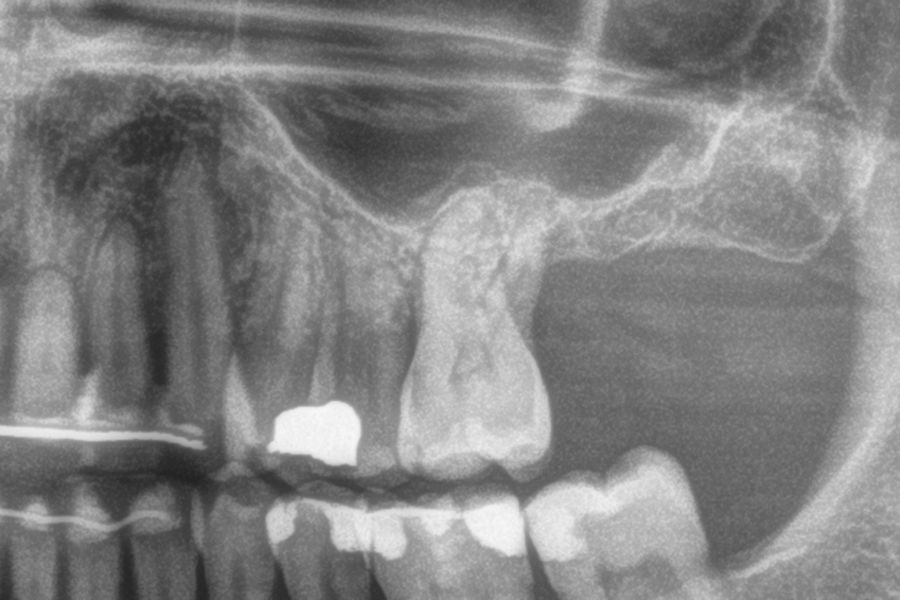

Figures 2-19 show one of the cases included in the study.

The mean height of the residual bone volume was 3.1 mm (+/- 0.3 mm with a range of 3-4 mm). In all cases, transcrestal sinus elevation was performed, with particulate autologous bone obtained from milling the neo alveolus generation zone for implant insertion, being the average of this elevation above the apex of the implant of 2.8 mm (+/- 0.99 range 1.9 -5 mm). In the CT control scan after one year of inserting the studied implants, the bone gain achieved was maintained, no decrease in the volume gained was observed, only three cases showed a decrease of between 0.4 and 0.5 mm of the initial volume at the end (Table).

Ten patients who met the inclusion criteria were recruited, in which 20 implants were inserted. Three of them were women with an average age of 72 (+/- 6 years). None of the patients were smokers at the time of surgery and did not have any active periodontal disease. The majority of the implants diameter included in the study was 5 mm (60%), followed by 4.5, 5.5 and 4.75 mm (13.33% each). The predominant length was 5.5 mm (86.6% of the cases), with 13.4% of the remaining implants with a length of 4.5 mm. The most common positions were for the second molars (molars 27 and 17) representing 55% of the cases.